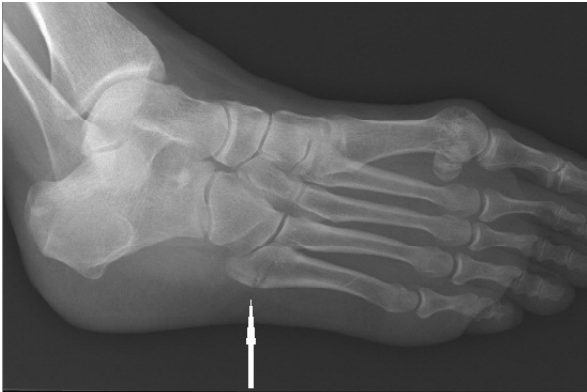

Describe what occurs in a jones fracture and what specific imaging is needed to detect it and distinguish from lateral ankle sprain

Fracture of diaphysis of 5th metatarsal, AP/Oblique/Lateral foot views with foot fully dorsiflexed required

Identify what part of the 5th metatarsal is affected in a jones fracture

Diaphysis